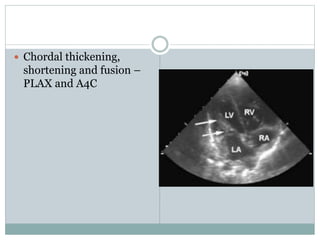

 Chordal thickening,

shortening and fusion –

PLAX and A4C